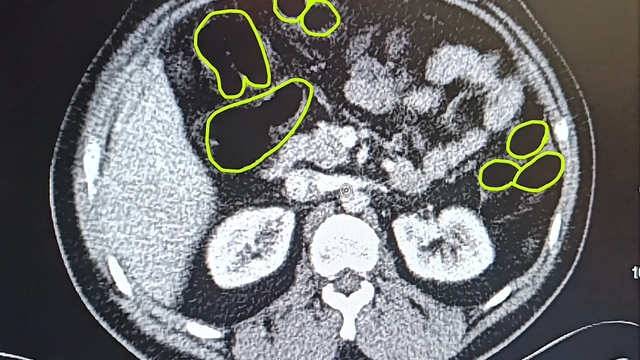

İl Jandarma Komutanlığı ekipleri, İran uyruklu A.O. (51), M.S. (37) ve P.S..'nin (28) ülkelerinden kente uyuşturucu getireceği bilgisine ulaştı. Şüpheliler Kocasinan ilçesi Himmetdede Mahallesi'nde taksi ile kente girmek istediği sırada durduruldu. Araçta yapılan aramada 15 gram esrar, 5 gram bonzai ve 117 adet uyuşturucu hap ele geçirildi. Gözaltına alınan 3 şüpheli muayene olmak üzere Kayseri Şehir Hastanesi'ne getirildi. Röntgen ve ultrason sonrası kontrollerde 3 şüphelinin midesinde uyuşturucu madde olduğu belirlendi. Şüphelilerin yuttukları uyuşturucuları kente sokmaya çalıştıkları tespit edildi. Kapsüller, sağlık ekibinin müdahalesiyle çıkarıldı. Taburcu edilen şüpheliler, İlçe Jandarma Komutanlığı'na götürüldü.